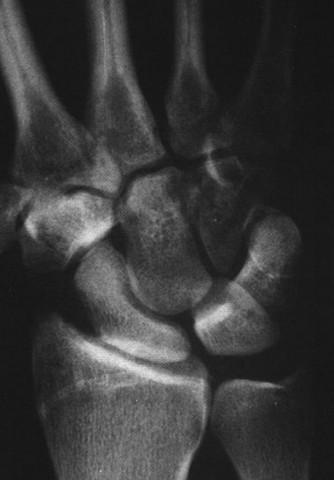

CASE 1 ### A 14-year-old patient presents with pain in the wrist after a fall. Examination reveals tenderness over the anatomical snuff box. X-ray picture is shown below (Fig. 3–1). What is the next course of treatment?

Figure 3–1(©) Sunil Thirkannad and Christine M. Kleinert.

The correct answer is (D). Injuries to the wrist with tenderness over the anatomical snuff box should raise the suspicion of a scaphoid fracture. Often, a scaphoid fracture may not be visible on initial x-ray pictures. It is prudent in such cases to suspect an “occult scaphoid fracture” and treat the patient in a splint. A repeat x-ray taken 2 to 4 weeks later can often reveal a fracture.